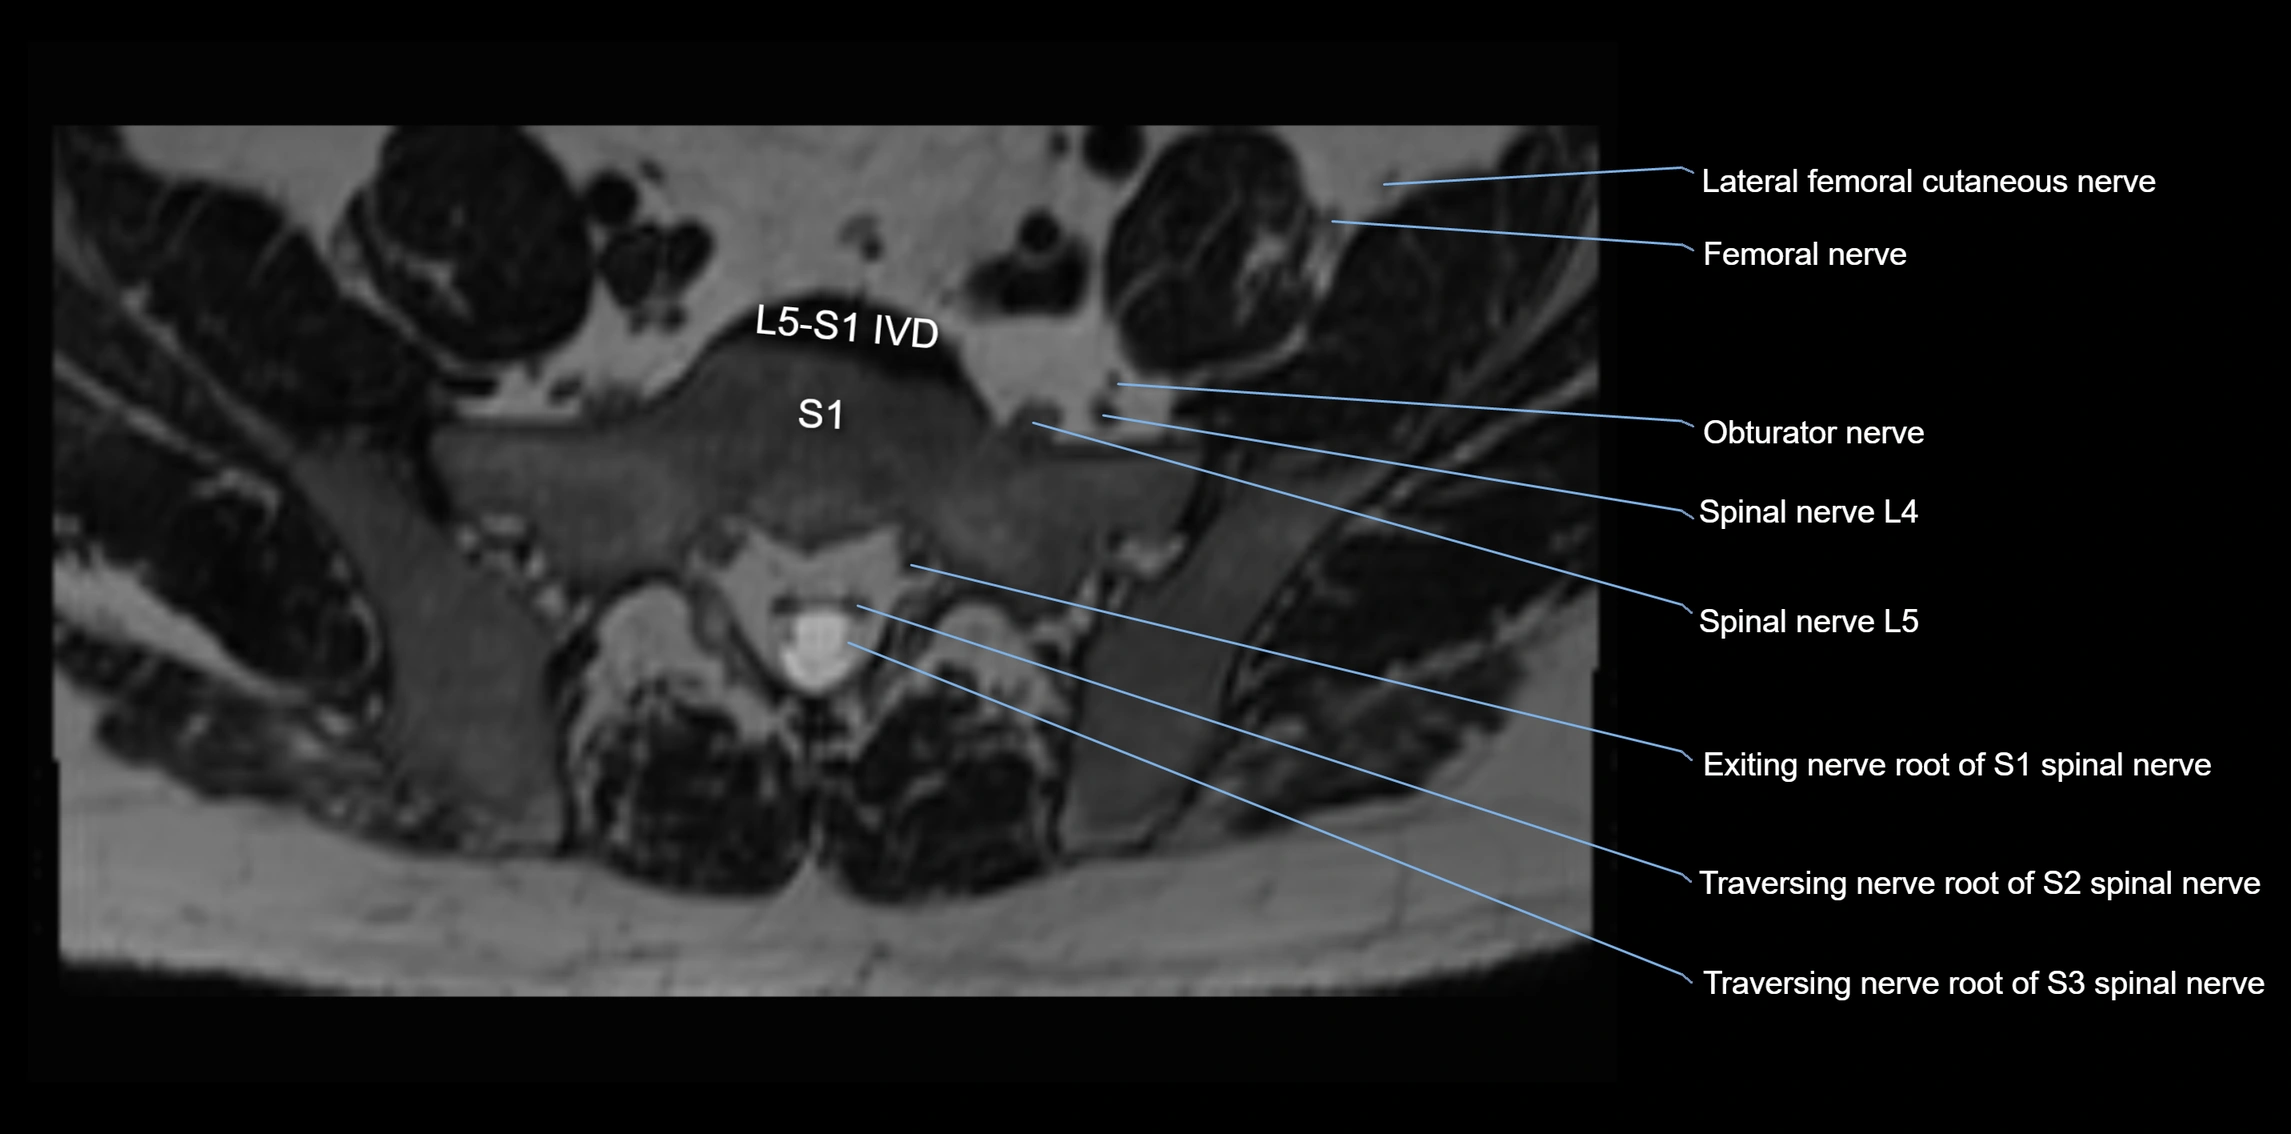

MRI image

image